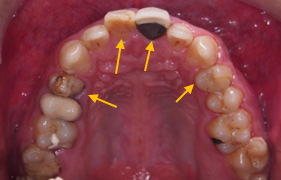

治療前 :前牙錯咬,上下排齒列不整,蛀洞大,左下缺牙空間大。

下排缺牙位置可以靠矯正關起來,省了一顆植牙的錢。但要矯正之前須要先處理好牙周,假牙問題。 讓我們矯正+牙周+假牙醫師相互配合吧!!!